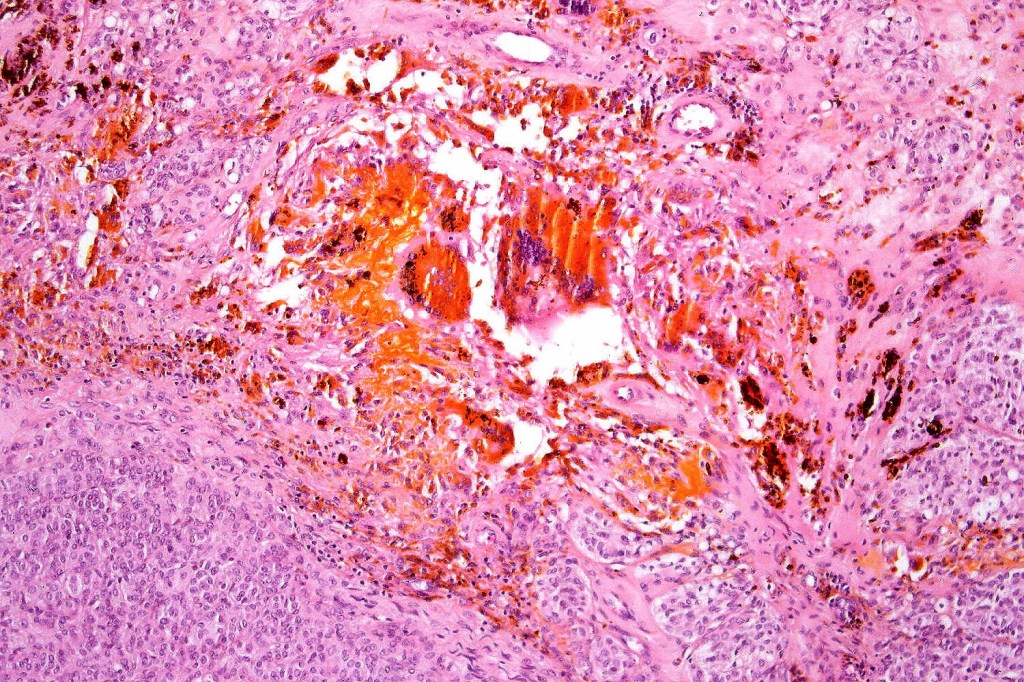

Cellular blue nevus

This uncommon most often devlops on the buttocks, sacrococcygeal region & distal extremities although it may be seen at just about any site. It shows a predilection for females and is diagnosed most often in the 2nd-4th decade. It presents as a blue-black/ or black nodule measuring 1-2 cm in dianeter. Similar to common blue nevus, the cellular variant can be encountered in a wide range of non-cutaneous locations.

Histological features

•Most characteristic is the dumbbell silhouette although a plague morphology may also be encountered

•Admixture of spindle cells, pigmented bipolar or dendritic cells & melanophages

•Stromal fibrosis, myxoid change, vascular hyalinization with cyst formation are often seen